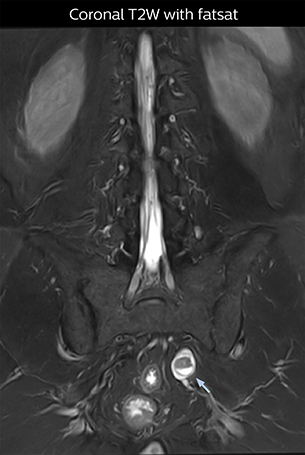

The key concept in MR neurography, Dr. Yabuki stresses, is the ability to directly visualize spinal nerves, versus inferring the presence of pathology indirectly. “Before NerveVIEW, we estimated compression of the nerve by looking for the presence or absence of fat signal on other MR images,” he says.

“For example, in sagittal images, when the presence of fat is observed in the intervertebral foramen, it suggests that there is a margin around the nerve. Similarly, the absence of fat indicates that the nerve is being compressed. So, we used to deduce nerve compression indirectly. With NerveVIEW, however, we can observe the condition of the nerves directly, regardless of the presence or absence of fat. We always prefer such direct observation of anatomy over having to make an inference about it.”

Distinguishing typical from atypical herniation informs the surgeon

“NerveVIEW is really useful for those cases where a nerve disorder is strongly suspected based on the clinical examination but our regular MRI images do not show any findings. These atypical herniations and spinal canal stenosis, occurring in 5% to 15% of the total lumbar herniation/stenosis cases are our main target when using NerveVIEW,” says Dr. Yabuki.

“Although symptoms of typical disc herniation and atypical hernia are very similar, the actual site of herniation is different. It is therefore important to characterize the nerve’s condition both inside and outside of the intervertebral foramina.

“Conversely, if we see no abnormality in NerveVIEW, we can assume at least that there is no severe condition that requires surgery. Like this, it can help us avoid unnecessary surgery. NerveVIEW can have a tremendous impact in this way.”